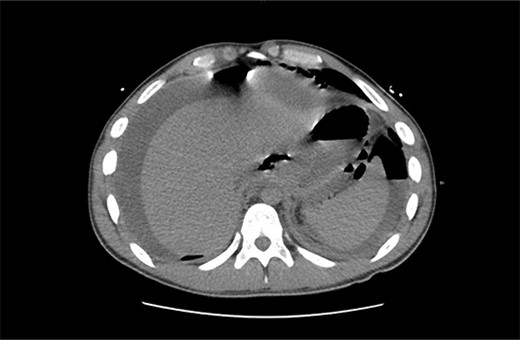

A 21 year old male presented to the emergency department with 1 day of abdominal pain and vomiting. Seven days earlier, a laparoscopic Nissen fundoplication, posterior cardiopexy, and anterior gastropexy for reflux aspiration were performed. Medical history included a left branchial cyst and asthma. Gastroscopy 3 years prior demonstrated reflux oesophagitis and small hiatus hernia, with no previous surgeries. On examination, blood pressure was 118/85 mmHg, with tachypnoea to 40 breaths per minute and tachycardia to 121 beats per minute. He was peritonitic. Laboratory results demonstrated C-reactive proteinof 543 mg/dL and Lactate of 5.9 mmol/L. He was commenced on intravenous fluid resuscitation and piperacillin-tazobactam. Computed tomography (CT) abdomen demonstrated large amounts of intra-abdominal free fluid, and more than expected pneumoperitoneum for laparoscopy performed 7 days prior, as seen in Fig. 1. Nasogastric tube (NGT) and indwelling urinary catheter were inserted, and the patient was organized for a damage control diagnostic laparoscopy +/− laparotomy.

Non-contrast CT abdomen/pelvis in axial view demonstrating diffuse intra-abdominal free fluid with multiple large locules of intraperitoneal free air.